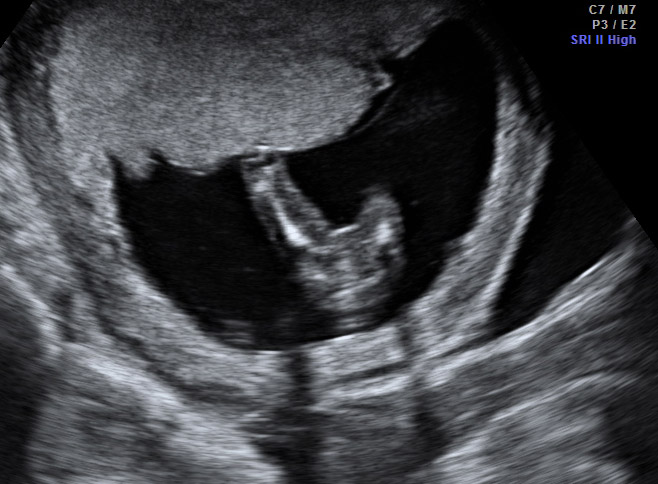

Had an elective u/s today @ 15 wks. Tech said girl, looking for some confirmation. The third pic has me a little confused, but she said that wasn't a good shot. Looking for you wonderful ladies to weigh in! TIA!! Attachment 23883Attachment 23884Attachment 23885